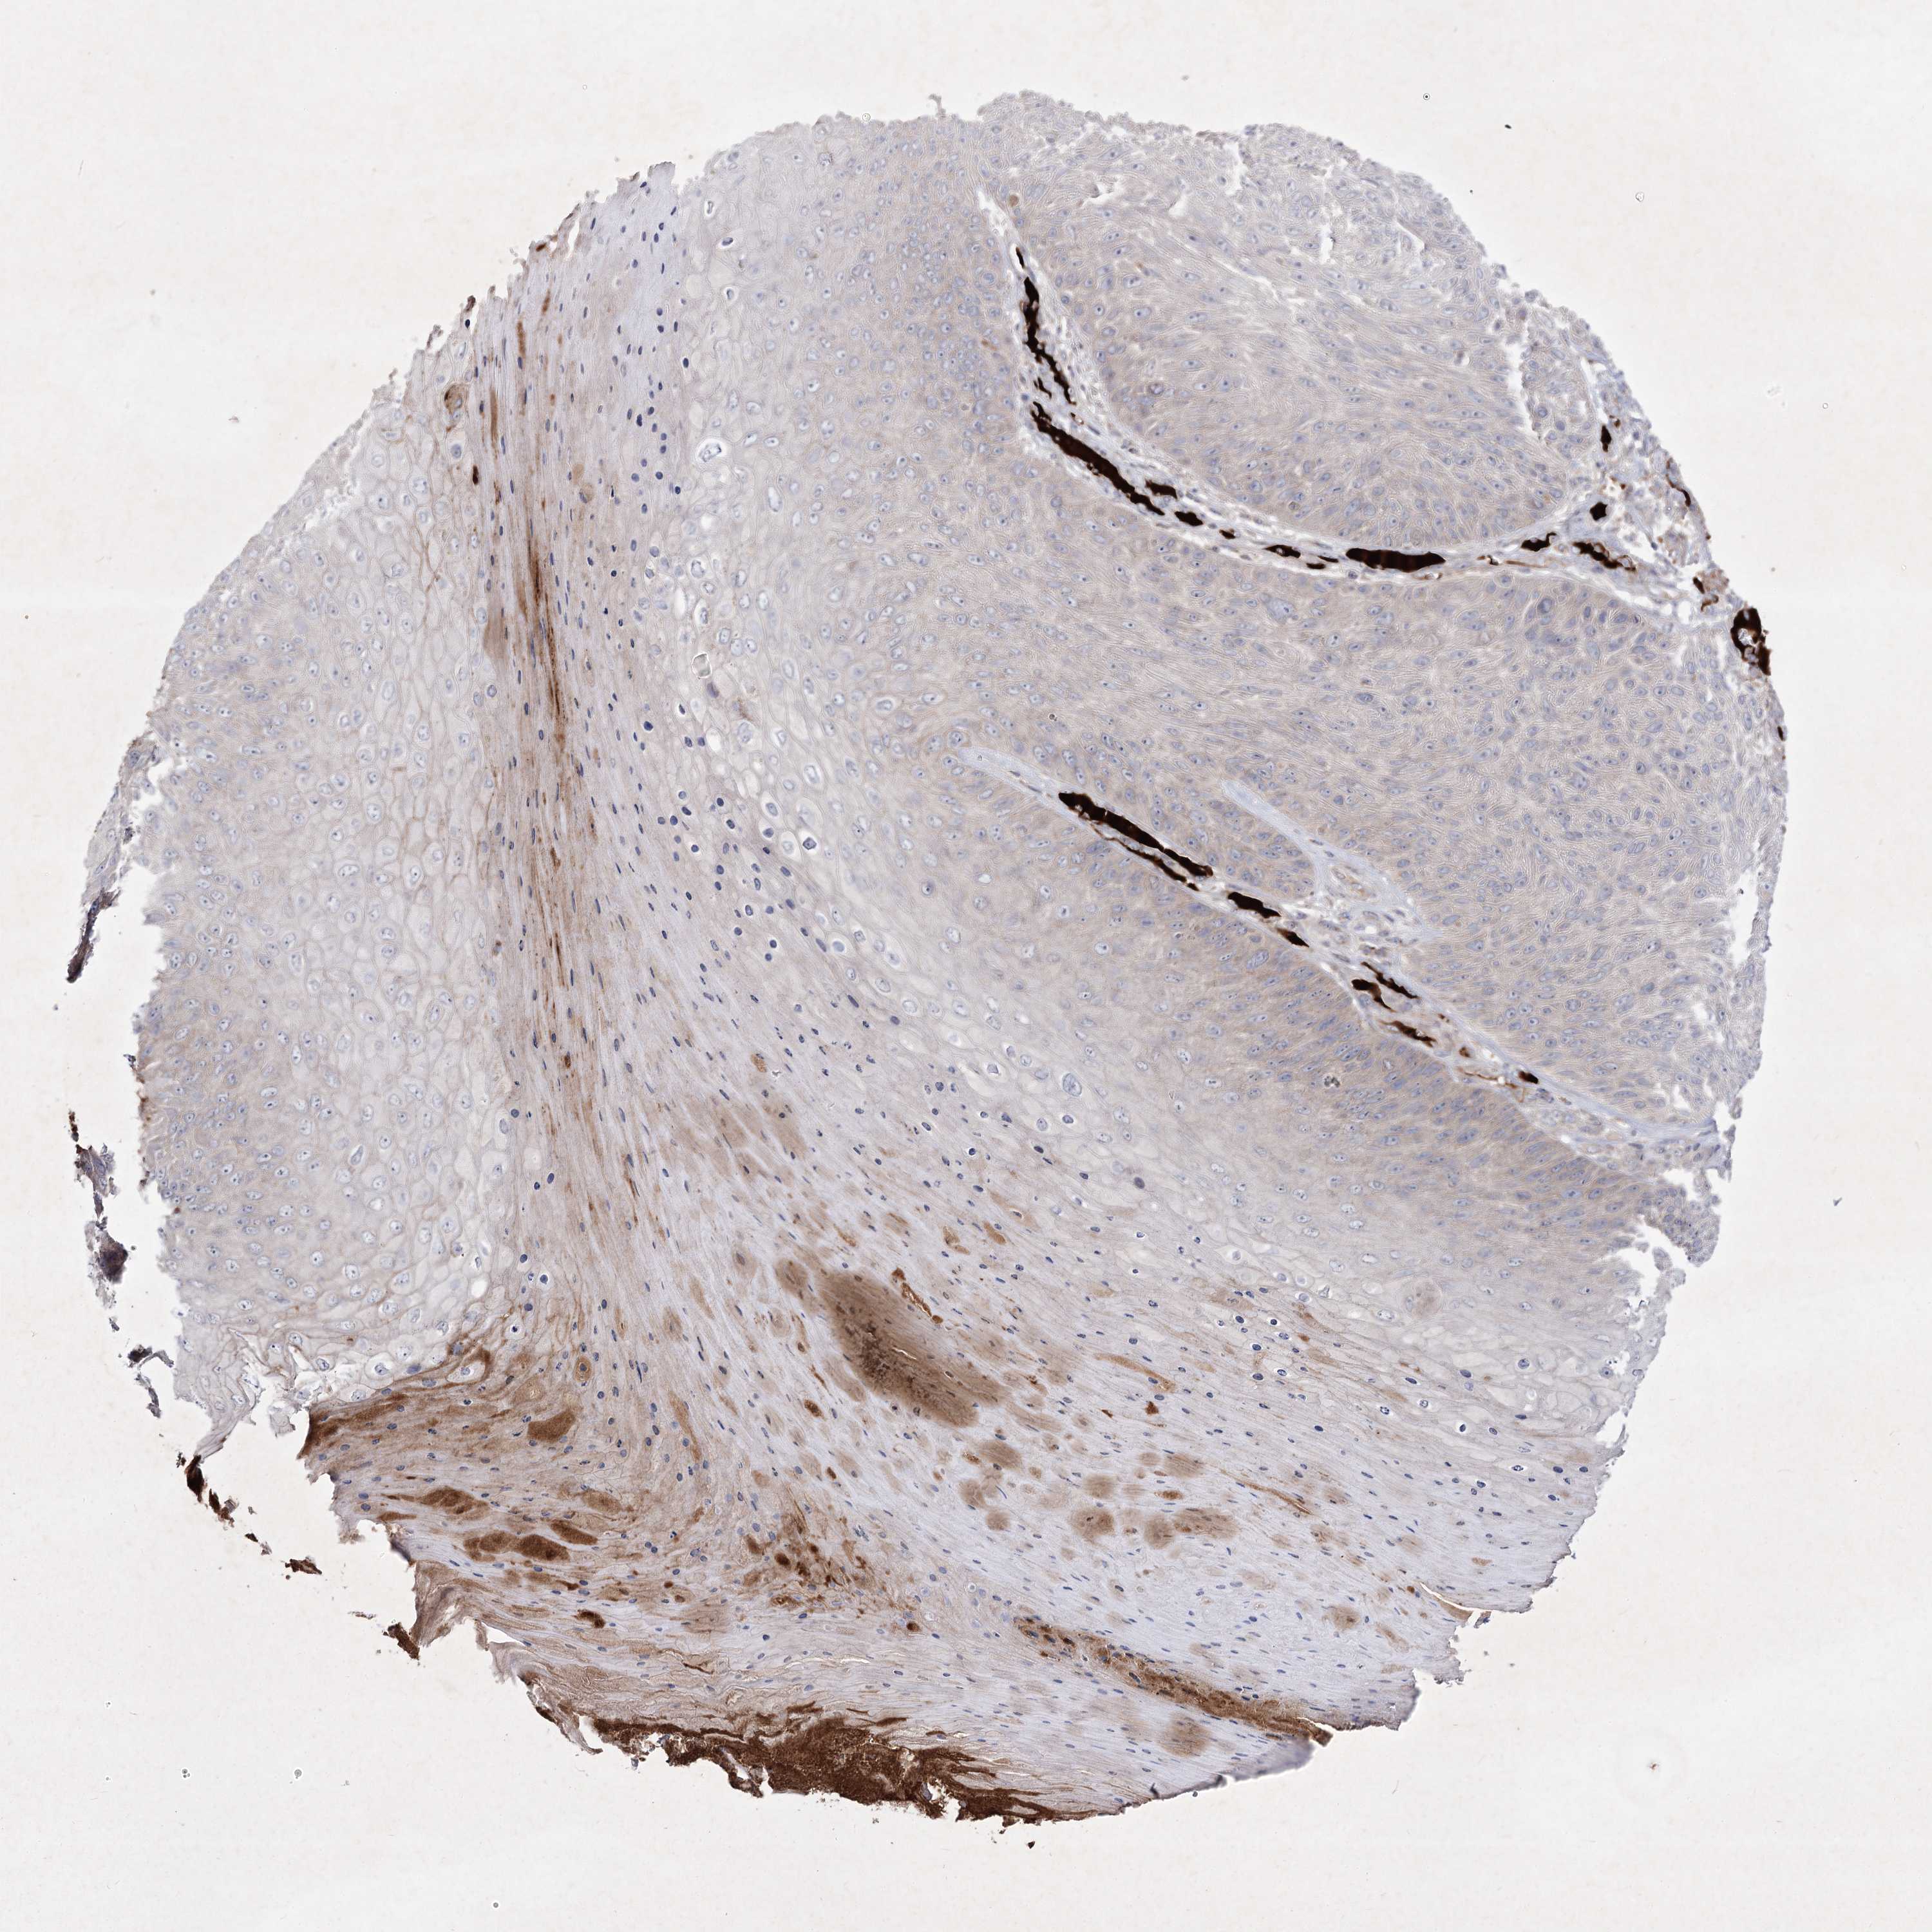

Basal cell and squamous cell cancer

SKIN CANCER - Protein expressioni

A mouse-over function shows sample information and annotation data. Click on an image to view it in a full screen mode. Samples can be filtered based on level of antibody staining by selecting one or several of the following categories: high, medium, low and not detected. The assay and annotation is described here.

Antibody stainingi

Antibody staining in the annotated cell types in the current human tissue is reported as not detected, low, medium, or high, based on conventional immunohistochemistry profiling in selected tissues. This score is based on the combination of the staining intensity and fraction of stained cells.

Each image is clickable and will lead to virtual microscopy that enables deeper exploration of all samples and also displays staining intensity scores, fraction scores and subcellular localization as well as patient and tissue information for each sample.

Antibody HPA036697

Staining

High

Medium

Low

Not detected

Intensity

Strong

Moderate

Weak

Negative

Quantity

>75%

75%-25%

<25%

None

Location

Nuclear

Cytoplasmic/membranous

Cytoplasmic/membranous,nuclear

Basal cell carcinoma